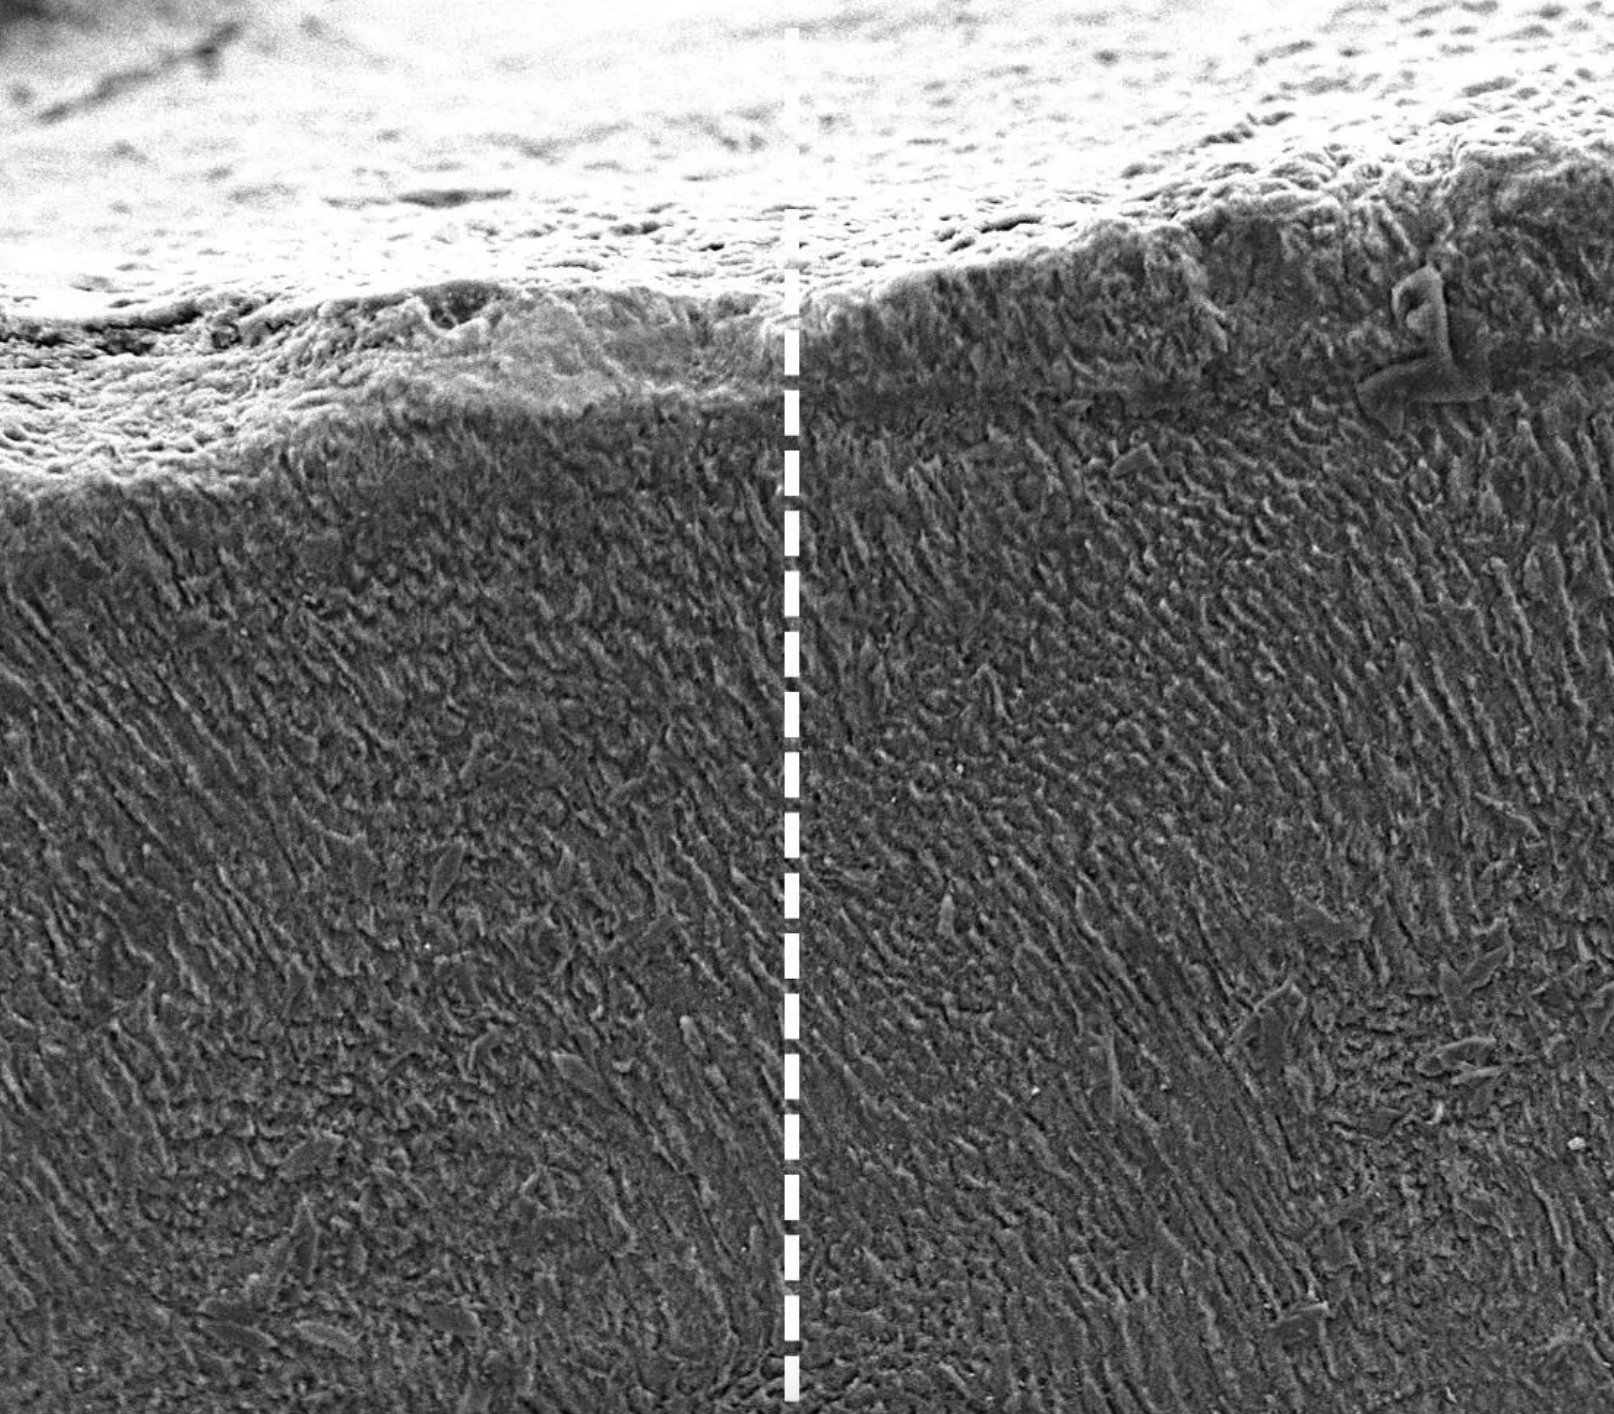

Mechanizmus je elegantne jednoduchý a využíva prirodzené procesy v tele. Po nanesení na povrch zuba vytvorí keratín vysoko organizovanú, kryštalickú štruktúru, ktorá funguje ako lešenie. Toto lešenie následne priťahuje ióny vápnika a fosfátu, ktoré sú prirodzene prítomné v slinách, a podporuje tak rast novej, hustej minerálnej vrstvy podobnej sklovine.

Táto nová vrstva nielenže chráni zub pred ďalším poškodením, ale účinne uzatvára aj odhalené nervové kanáliky. Práve tieto kanáliky sú príčinou nepríjemnej citlivosti zubov, takže liečba poskytuje nielen štrukturálnu opravu, ale aj okamžitú úľavu od symptómov. Týmto spôsobom sa zubárstvo posúva od mechanických opráv, ako sú plomby, k biologickej regenerácii.